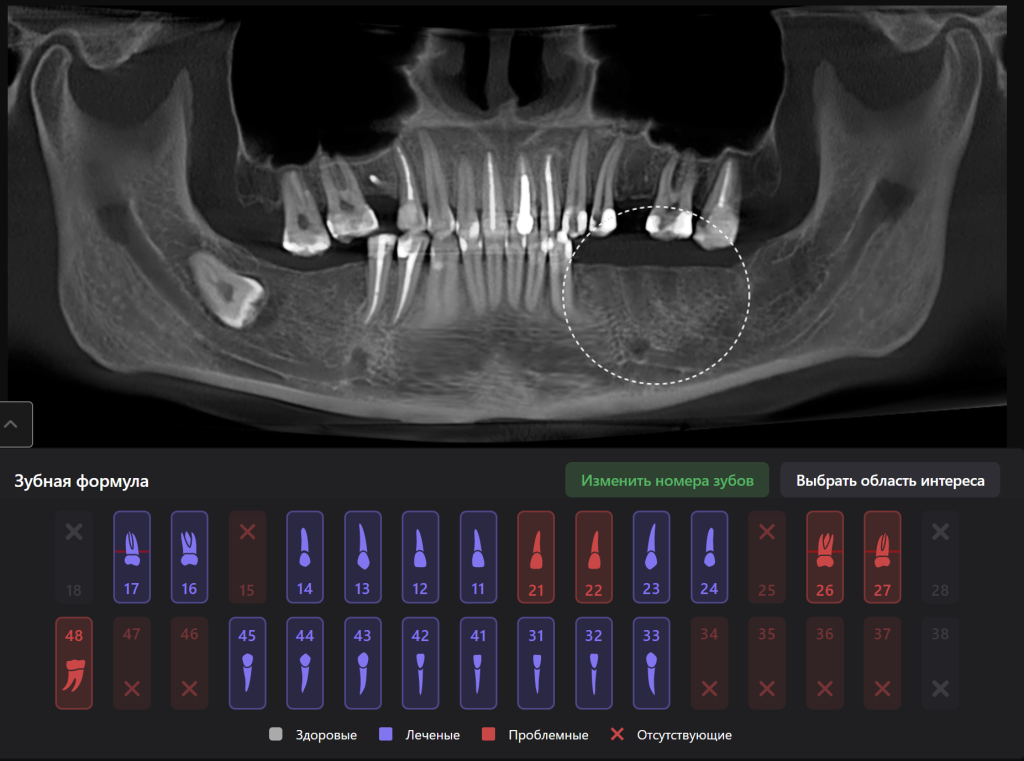

Panoramic reconstruction from CBCT